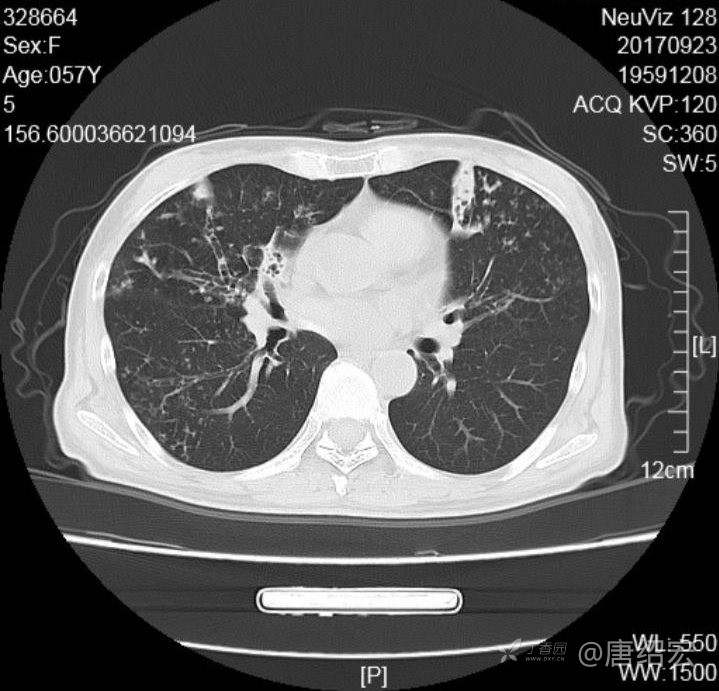

女,57岁,

主诉:发热、咳嗽、咯黄痰,胸闷3天入院。

铜绿假单胞菌性肺炎 (12)

铜绿假单胞菌感染 (20)